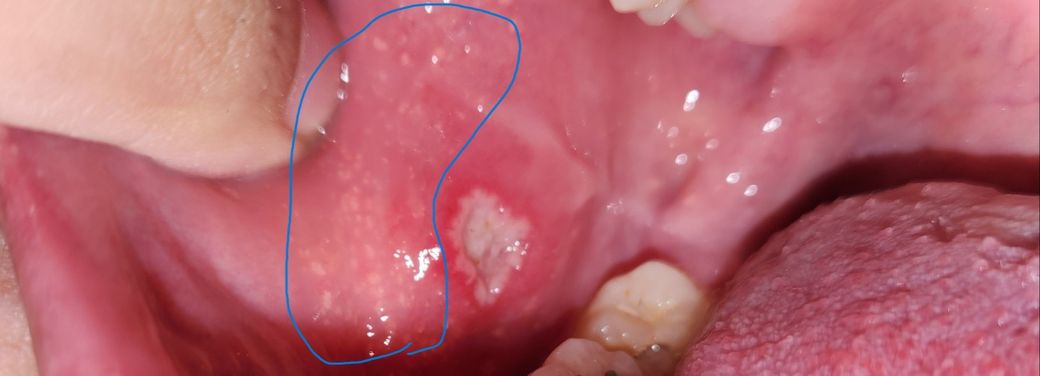

(혐)볼 안쪽에 구내염과 이상한 좁쌀 같은 염증?

구내염은 원래 자주 생기는데... 이번엔 보니 근처에 하얗게 좁쌀같은 점들이 보입니다..

이게 뭔가요? 어떤 질환이나 의심되는 다른 병의 증상인가요?

구내염 옆의 좁쌀같은 병변은 포다이스반이라 추정되고, 피지샘이 없어야 할 위치에 있어서 보이는 병변이니 문제가 되지는 않습니다. 가까운 이비인후과에서 확인해보시면 되겠습니다.